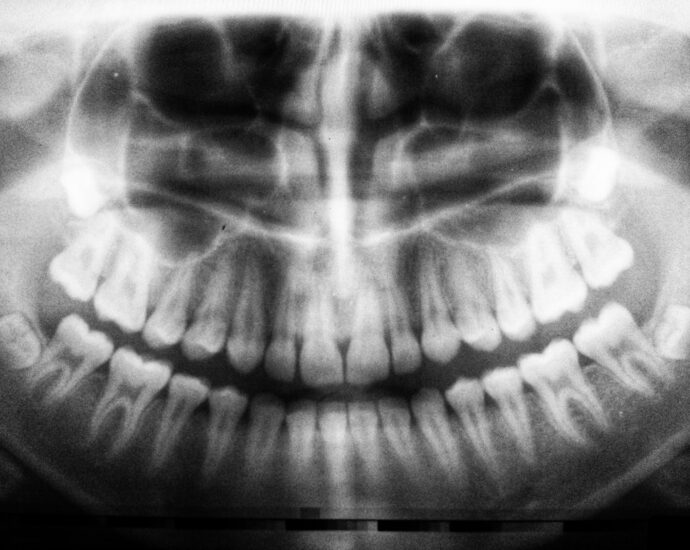

Photo Dental X-ray